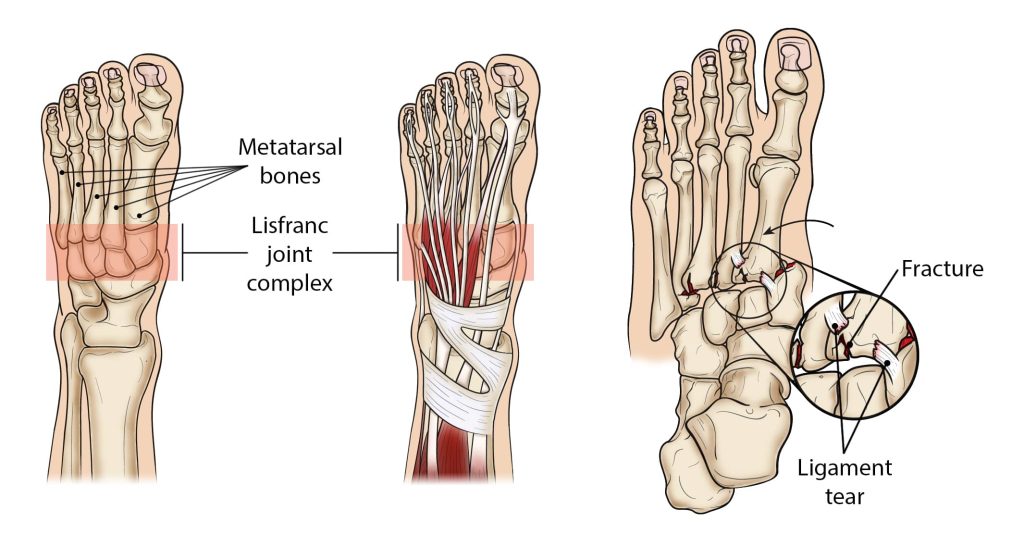

Lisfranc (midfoot or tarsometatarsal joint) injuries result when the bones in the midfoot are broken or ligaments that support the midfoot are torn. The severity of the injury can vary from simple to complex, involving many joints and bones in the midfoot.

Unstable Lisfranc injuries result in displacement of some or all the tarsometatarsal joints with associated ligament rupture and/or significant fractures. Unstable injures are commonly managed operatively where the bones are fixed with screws, pins, or k-wire to allow for the injury to heal in a stable position. Fusion of this joint is also another operative management option.